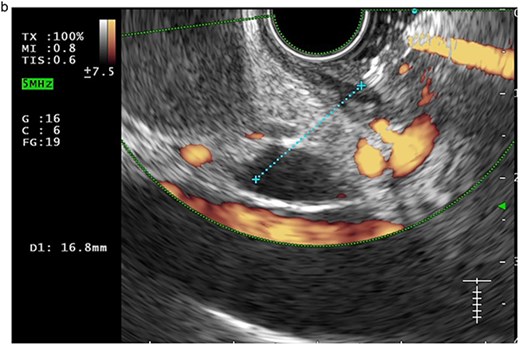

In view of the ongoing leakage and the hostile operative field, a third intervention was undertaken on postoperative day 24 following the second surgery. After multidisciplinary discussion, a combined surgical–endoscopic approach was undertaken in collaboration with internal medicine specialists. Intraoperative findings revealed dense adhesions from prior surgeries and a 0.5-cm perforation at the proximal duodenal stump, located near the ampulla of Vater. Initial endoscopic retrograde cholangiopancreatography (ERCP) was unsuccessful due to limited ampullary access; thus, EUS-CDS with ENBD placement was performed as an alternative strategy. From the duodenal bulb, the common bile duct (CBD) measured 4.7 mm on EUS, and Doppler confirmed no intervening vessels (Figs 4a and 4b). A 19-gauge EZ Shot 3 needle (Olympus) was used to puncture the extrahepatic bile duct, and bile aspiration followed by contrast injection confirmed correct positioning (Fig. 4c). A VisiGlide 2 angled guidewire (0.025 inch) was advanced into the right intrahepatic duct, and the tract was dilated using an ES dilator. A 7-Fr ENBD catheter was subsequently deployed across the choledochoduodenostomy under fluoroscopic guidance, achieving effective biliary drainage (Figs 4d and 4e). In addition, a 16-Fr Foley catheter was inserted into the duodenal perforation as a duodenostomy tube (Fig. 4f) for external drainage, and six closed wound vacuum drains were placed for peritoneal irrigation and drainage.